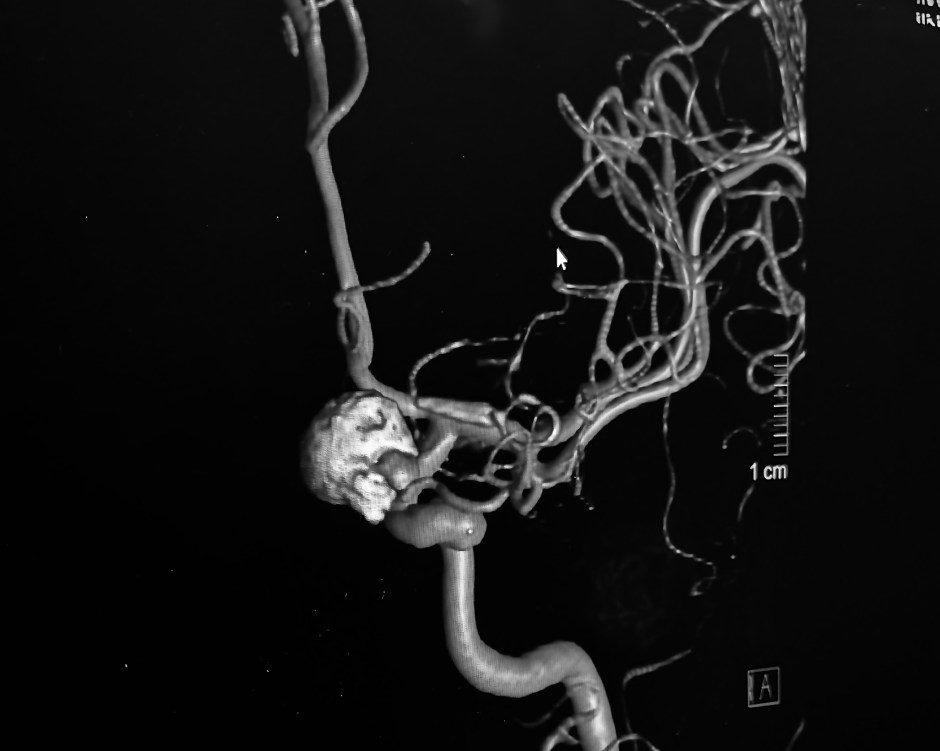

I was able to grab a screen capture of the latest angiogram images in the doctor’s office. Really fascinating to see the large 11mm original aneurysm filled with coils showing as a large gray mass. Then to see how close the clip actually is to the first aneurysm. As Dr. Ecker said, neurologically speaking “it’s in another room.” due to the microscopic aspect of their work. He also pointed out where the infundibulum is. It looks big to me, but it’s only around 3.7mm.